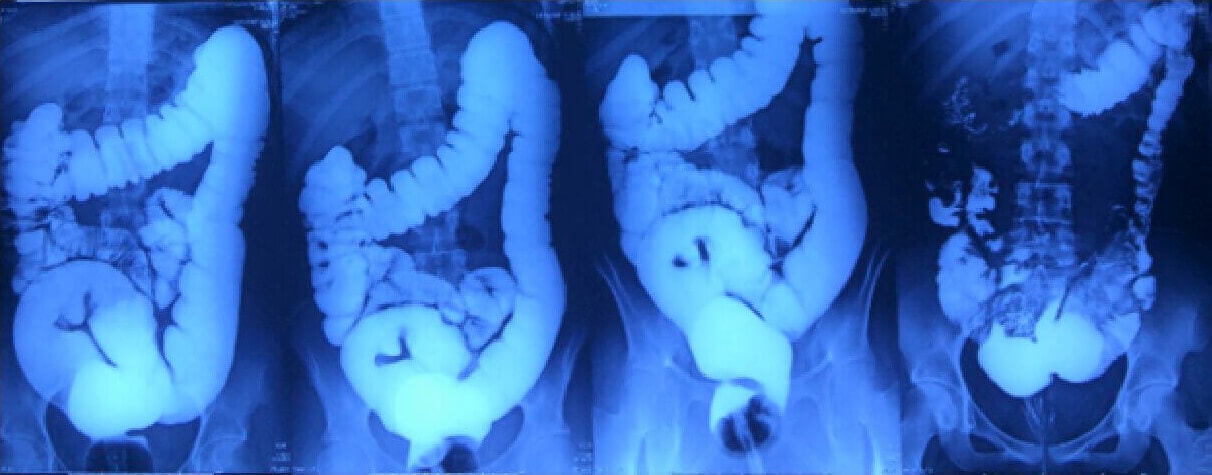

Comprehensive Evaluation and Diagnosis: When seeing a patient with constipation symptoms, medical history, digestive diseases, Dr. Astha Bhatt follows a meticulous evaluation process to identify the underlying cause. The evaluation typically involves a detailed discussion about the symptoms, review of medical records, physical examination, and may include diagnostic tests such as colonoscopy, defecography, or transit studies. By conducting a thorough evaluation, Dr. Bhatt can tailor the treatment plan to address the specific needs of each patient.

When seeing a patient, Dr. Astha Bhatt follows a meticulous evaluation process to identify the underlying cause. This evaluation typically involves a detailed discussion about the symptoms, review of medical data, physical examination, and may include diagnostic tests such as colonoscopy, defecography, or transit studies. By conducting a thorough evaluation, Dr. Bhatt can tailor the plan to address the specific needs of each patient.